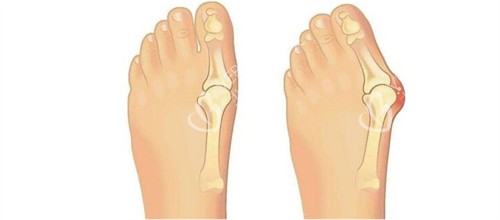

拇外翻矫正手术

拇外翻,俗称大脚骨,是更常见的足部问题之一。苏敬达医生针对拇外翻的矫正手术,根据病情轻重分为三档:

轻度拇外翻矫正手术:费用从16800元起。轻度患者,拇趾外翻角度较小,手术难度相对较低,改善也更快。

中度拇外翻矫正手术:费用从19800元起。中度患者,拇趾外翻角度较大,需要更精细的手术操作和更长的改善期。

重度拇外翻矫正手术:费用从22800元起。重度患者,拇趾外翻严峻,可能伴有其他足部问题,手术复杂度和风险相应增加。